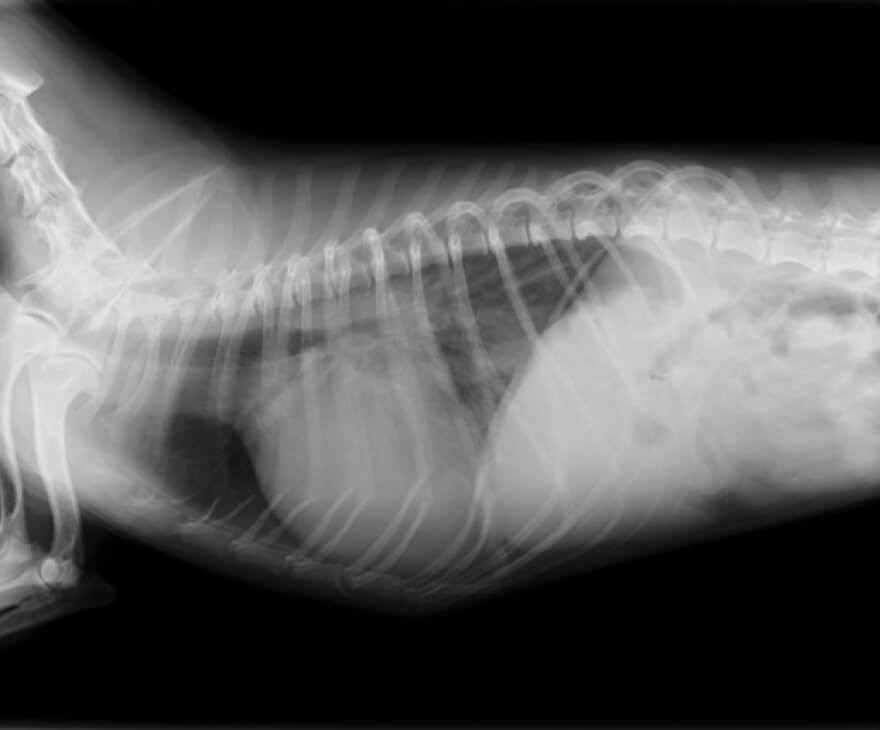

肥大型心筋症 (HCM:Hypertropied Cardiomyopathy )

猫の心疾患として、臨床的に最も多く遭遇します。

左心室心筋が内側に向かって厚くなることが特徴です。

心臓自体の大きさの変化は少なく、臨床徴候も乏しいため、通常の健康診断では発見が困難です。心筋肥大の場所により、『通常の肥大型心筋症』と『閉塞性肥大型心筋症( HOCM )』に分類されます。

HCMによる胸水

HCMによる肺水腫